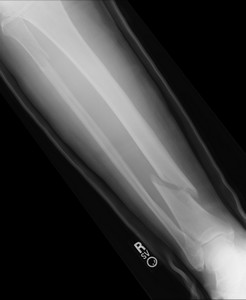

essa imagem contém somente fraturas agudas

As Fraturas de Stress mais comuns ocorrem nos membros inferiores, ou seja, nos pés, pernas, coxa e bacia, mas determinados esportes apresentam incidência de lesões em membros superiores (por exemplo, nas costelas em remadores, no antebraço em esportes de raquete, dentre outros).